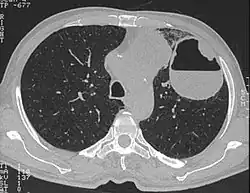

Spiegelbildungen (medizinisches Englisch „air-fluid level“ oder „fluid-fluid level“) werden auf Röntgenaufnahmen z. B. des Abdomens und in Schnittbildverfahren wie CT und MRT beobachtet. Es sind horizontale Grenzflächen zwischen Materialien von unterschiedlicher Dichte, bei denen das schwerere Material mit der Schwerkraft absinkt. Es gibt Gas-Flüssigkeit-Spiegel und Flüssigkeit-Flüssigkeit-Spiegel (etwa in einer alten Blutung, wenn die festen Bestandteile absinken).

Spiegel beweisen das Vorliegen von freier Flüssigkeit, z. B. in Hämatomen, Knochenzysten[1] und einschmelzenden Tumoren.[2] Luft/Sekret-Spiegel in den Nasennebenhöhlen weisen auf Sinusitis hin. Luft/Flüssigkeits-Spiegel im Brustkorb gibt es beim Hämatothorax oder Serothorax. Abszesse mit Spiegeln haben entweder Anschluss an die Luftwege oder den Darm bekommen, oder sie werden durch Gasbildner verursacht. Ein einzelner Spiegel im Mittelfell (Mediastinum) liegt in der Regel in einem Magenanteil, der in den Brustkorb verlagert ist, als Magenhernie oder nach operativem Magenhochzug.[3] Luft-Flüssigkeitsspiegel im Darm entstehen durch verzögerte Darmpassage des Stuhls und sind in höherer Anzahl ein Anzeichen für einen Ileus.[4]